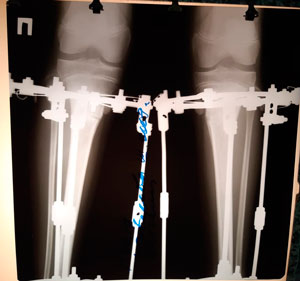

Дата операции - 16.04.2019г.

Дата операции - 12.06.2019г.

Срок сращения - 56 дней.

Рентген перед снятием аппаратов.

IMG_3589-12-06-19-11-49.JPG

IMG_3590-12-06-19-11-49.JPG